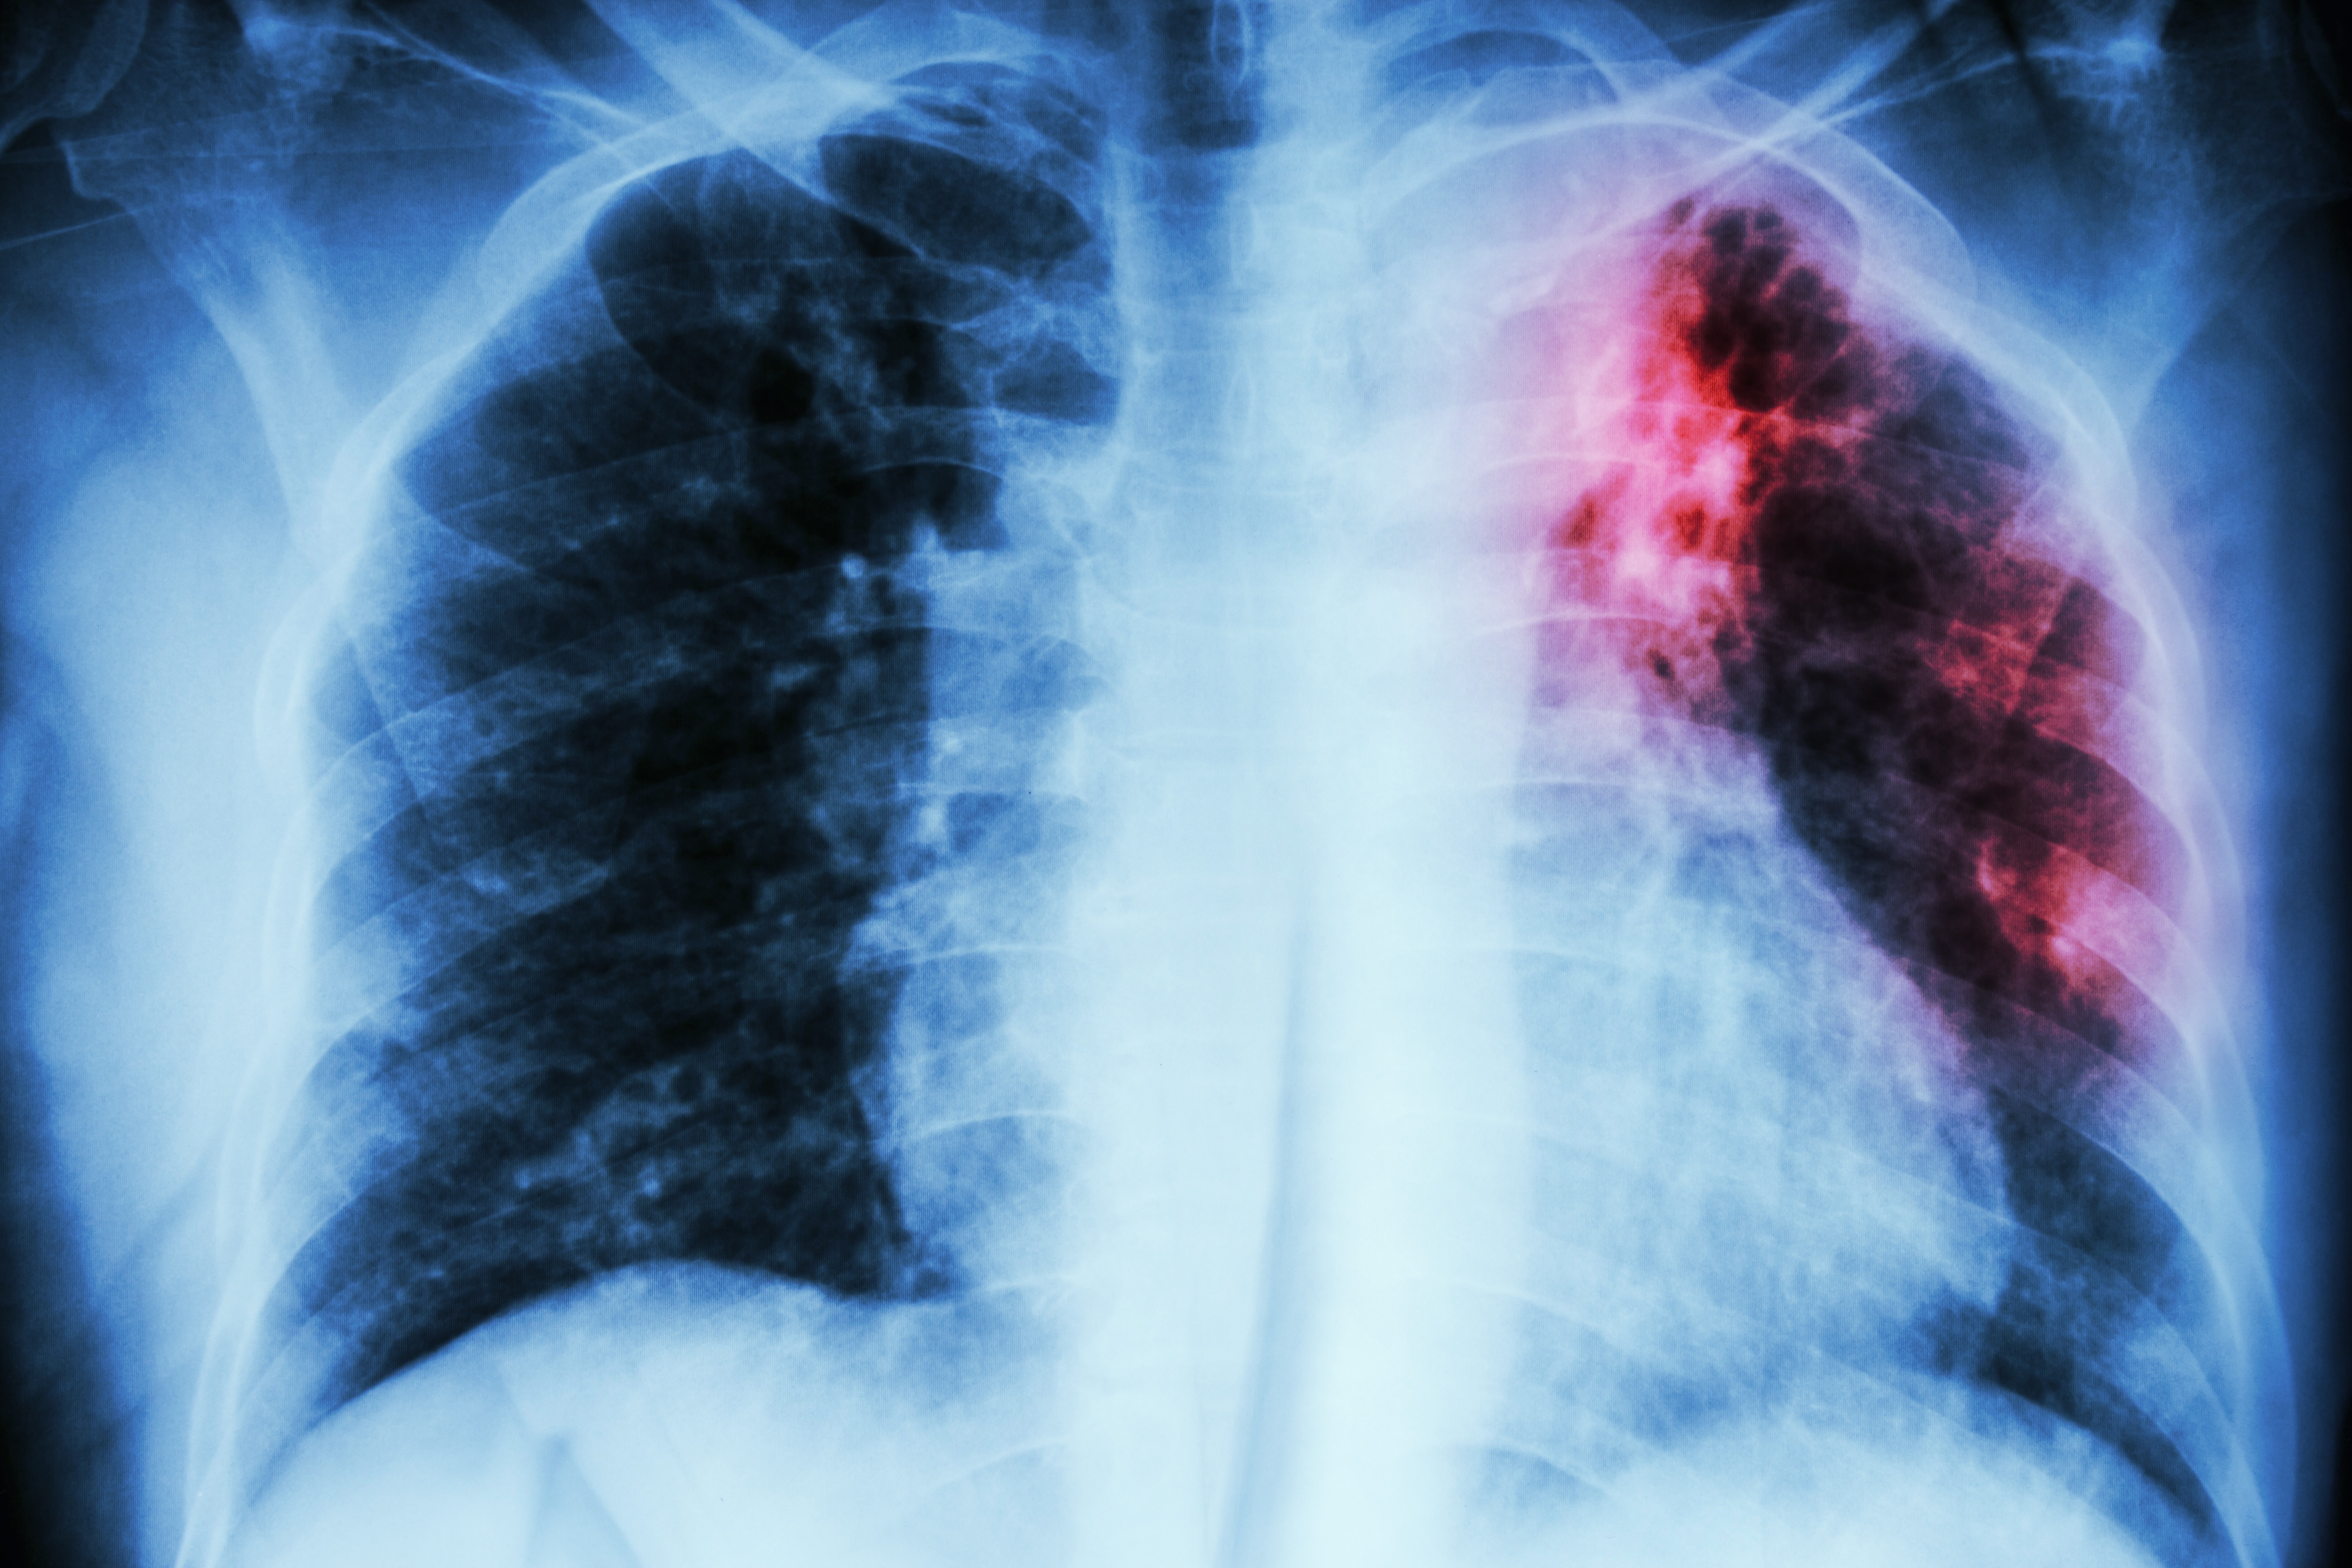

Лица с употреблением психоактивных веществ (ПАВ) подвержены заболеванию туберкулёзом, с развитием болезни в тяжелых деструктивных формах с массивным бактериовыделением.

Сочетанная патология (туберкулёз и алкоголизм, туберкулёз и наркомания) представляют большую эпидемиологическую опасность, чаще всего распространяя микобактерии туберкулёза, устойчивые к противотуберкулёзным препаратам.